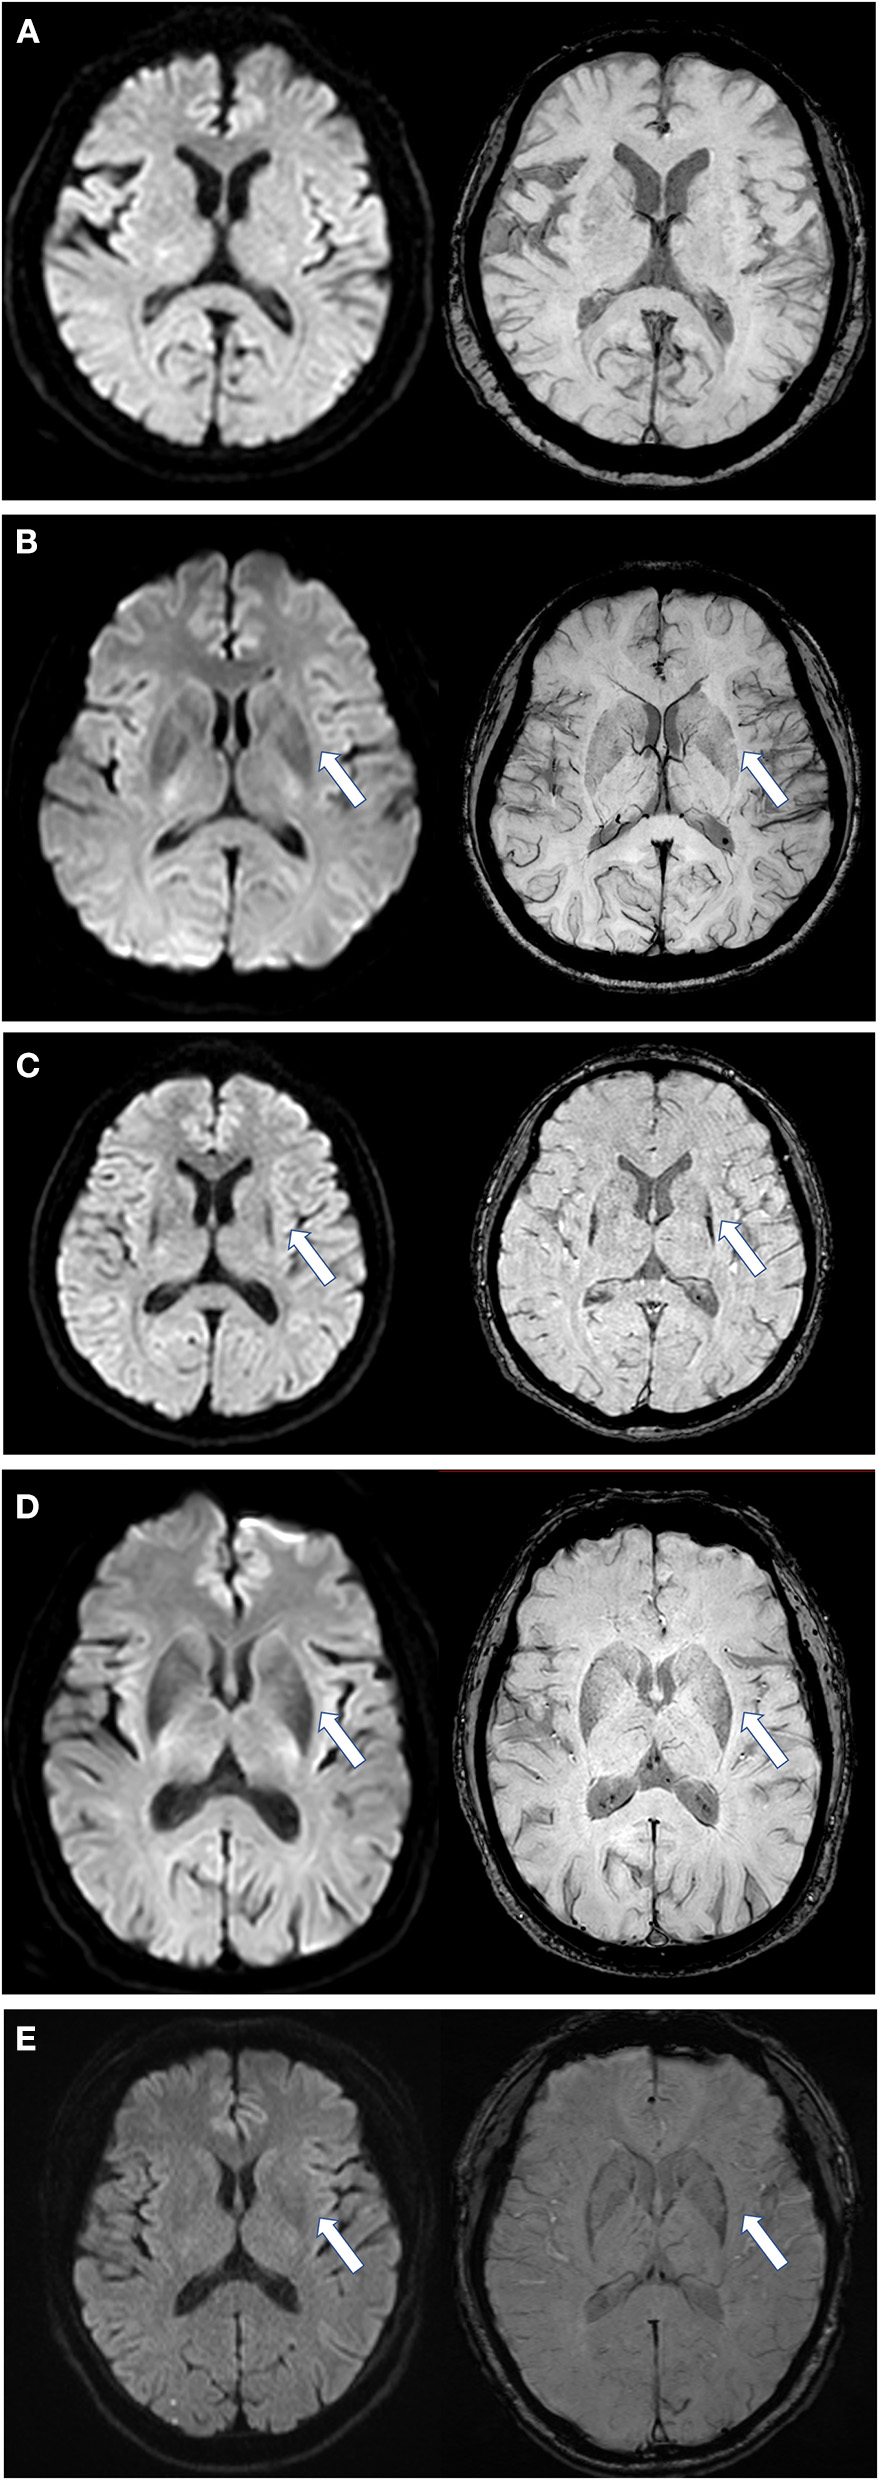

First, we assessed the margin of the putamen on DW images, the evaluation of which was similar to SWI assessment (Figure 1) (12): Score of 0: the intensity was normal, no hypointense signal was observed; Score of 1: the intensity was similar to cerebrospinal fluid and without a posterolateral gradient; Score of 2: the intensity was similar to cerebrospinal fluid with a posterolateral gradient; Score of 3: the intensity was similar to cerebrospinal fluid with a marked gradient of posterolateral to anteromedial hypointensity. A hypointense signal score over 2 in the putamen margin was considered a criterion for an MSA diagnosis. If the scores of the two sides (right/left) differed, the higher score of the unilateral side and the mean score of both sides were calculated separately. The scores were graded previously to the imaging analysis. Second, we assessed the shape of the putaminal margin hypointensity in subjects with a score ≥2. If the low signal at the edge of the putamen showed a straight distribution (the “black straight-line sign”), it was considered a criterion for diagnosing MSA. If the low signal at the edge of the putamen was distributed in an arc, it was considered as a non-MSA abnormal signal (Figures 1, 2).

Figure 1. Scores of putaminal hypointensity in DWI and the corresponding SWI sequence. Left, DWI sequence; right, SWI sequence. (A) DWI and SWI score are all 0 as shown by an arrow; (B) DWI and SWI score are all equal to 1; (C) DWI and SWI scores are all 2 points, and in a straight distribution; (D) DWI and SWI scores are all 2, but with an arc shape and an unclear boundary; (E) from a PD patient, with a DWI score of 1 and SWI score of 2. DWI, diffusion-weighted imaging; SWI, susceptibility-weighted imaging. All illustrations are denoted as arrow.